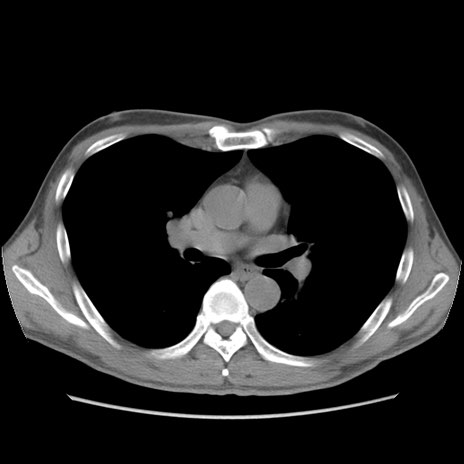

症例56 CT(横断像)

脂肪ウインドウ